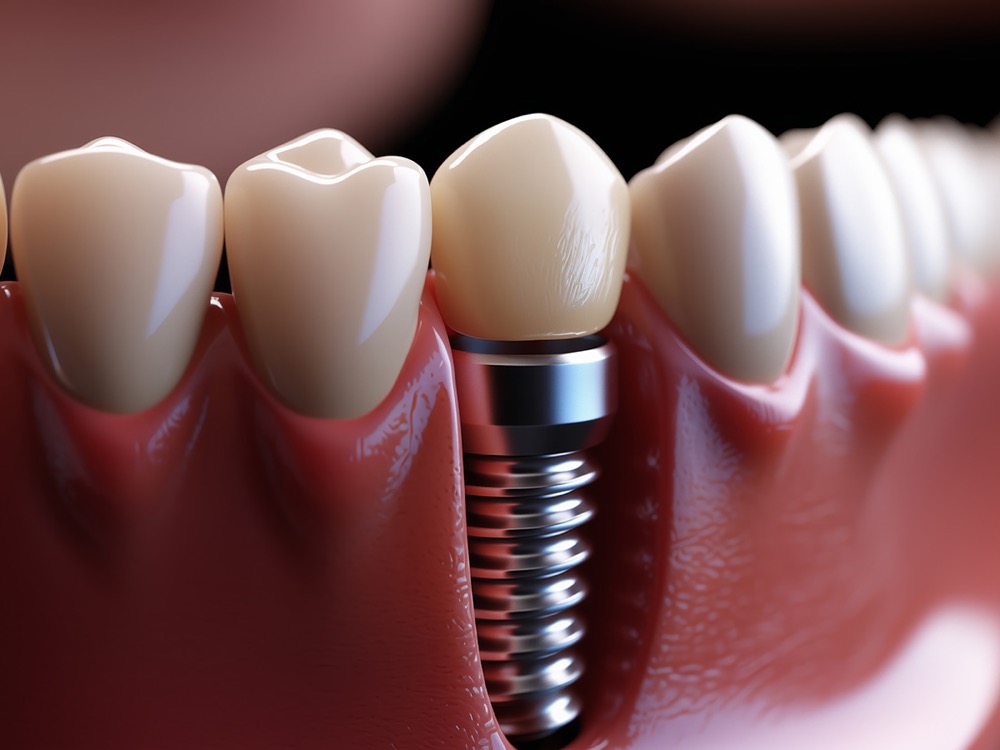

IMPLANTOLOJİ

IMPLANTOLOJİDiş Implantı

Eksik dişlerin yerine titanyum vidalar aracılığıyla yerleştirilen kalıcı ve doğal hissettiren çözüm.